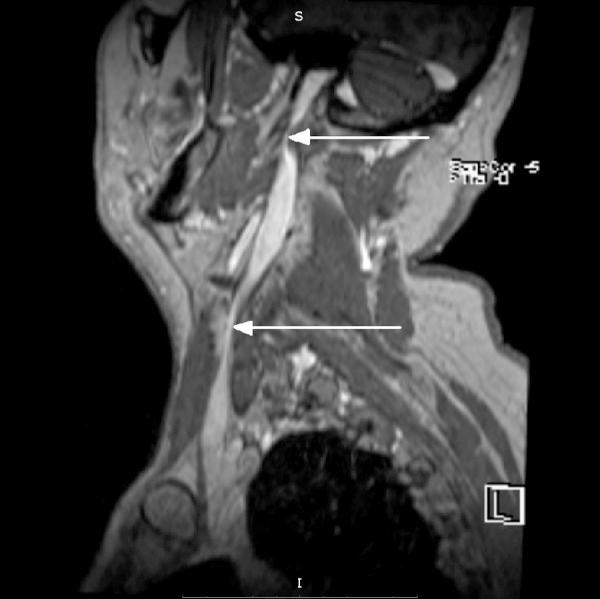

慢性脑脊髓静脉功能不全与多发性硬化症之间存在关联吗?——一项批判性综述。

Is there any relation between chronic cerebrospinal venous insufficiency and multiple sclerosis? - a critical review.

Summary Though the etiology of multiple sclerosis remains unknown, the widely accepted explanation is that it has an autoimmune inflammatory background. In 2006 Paolo Zamboni renewed the somewhat forgotten vascular theory of the pathogenesis of multiple sclerosis, proposing the new entity of 'chronic cerebrospinal venous insufficiency'. As a result of this hypothesis, Zamboni suggested an endovascular treatment for multiple sclerosis involving venoplasty of the internal jugular vein and the azygos vein. Unfortunately, several teams have tried to replicate Zamboni's results without success. In this review, we present a chronological description of the results of the studies conducted by Zamboni and the later attempts to replicate his work. The main conclusion is that, taking into account results that are currently available, we should remain cautious and routine use of this treatment in patients should not be advisable.

摘要 尽管多发性硬化症的病因尚不清楚,但被广泛接受的解释是它具有自身免疫性炎症背景。2006年,保罗·赞博尼重新提出了某种程度上被遗忘的多发性硬化症发病机制的血管理论,提出了“慢性脑脊髓静脉功能不全”这一新概念。基于这一假说,赞博尼建议对多发性硬化症采用血管内治疗,包括颈内静脉和奇静脉的血管成形术。不幸的是,几个研究团队试图重现赞博尼的结果,但均未成功。在本综述中,我们按时间顺序描述了赞博尼所开展研究的结果以及后来试图重现其研究成果的情况。主要结论是,考虑到目前可得的结果,我们应保持谨慎,不建议在患者中常规使用这种治疗方法。